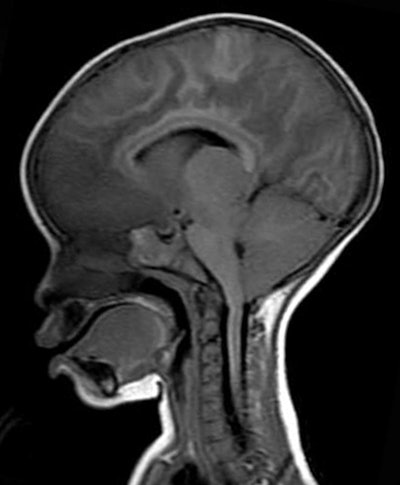

MR image shows increased brain volume in a 19-month-old girl with retinopathy-positive cerebral malaria.Because of the pressure on the foramen magnum, the retinopathy-positive patients with cerebral malaria inevitably died because they stopped breathing.

While the MRI scan at autopsy revealed a swollen brain, there was no evidence of severe expansion. However, the MRI acquired during the first 24 hours after admittance showed clear evidence of the brain pushing down through a narrow hole, known as the foramen magnum, at the base of the skull.

"That area gets mushed and compressed if the brain is pushed out, and causes breathing to stop," Taylor said. "We would always look for that, but we never saw it. We could see it on the MRI and we instantly knew what happened. We never, ever would have seen it had we not captured it during life with the MRI."